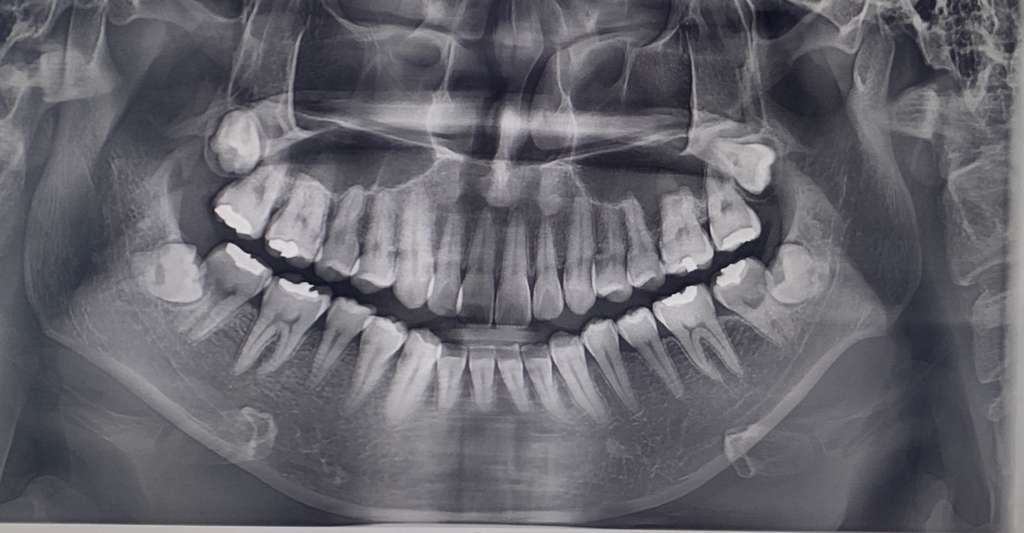

엑스레이 사진상 충치가 있는지 궁금합니다

엑스레이 사진에 충치가 있는 지 궁금합니다.

이렇다 한 통증은 없습니다만

일반인이라 충치 보는 법을 알아도

잘 색별해낼 수가 없더라구요

궁금합니다.

• 1번 째 사진

엑스레이 상으로 치아 사이에 충치가 의심되는 부분이 몇군데 잇기는 하지만, 정확한건 더 작은 엑스레이 사진을 찍어봐야 알것같습니다.

엑스레이상이 큰 충치는 없어보입니다.

이전에 충전한 재료 주변에 방사선투과성이 보이기는 하는데 이부위는 육안으로 직접 확인을 해야 알수 있을것 같아요.

엑스레이상으로는 충치를 확인하기는 어려우며, 육안으로는 표면에 검은색으로 썩은부위가 나타납니다. 하지만 육안으로 충치가 구분이 어려울수 있기에 보다 정확한 진단을 위해 치과진료를 받길 권합니다